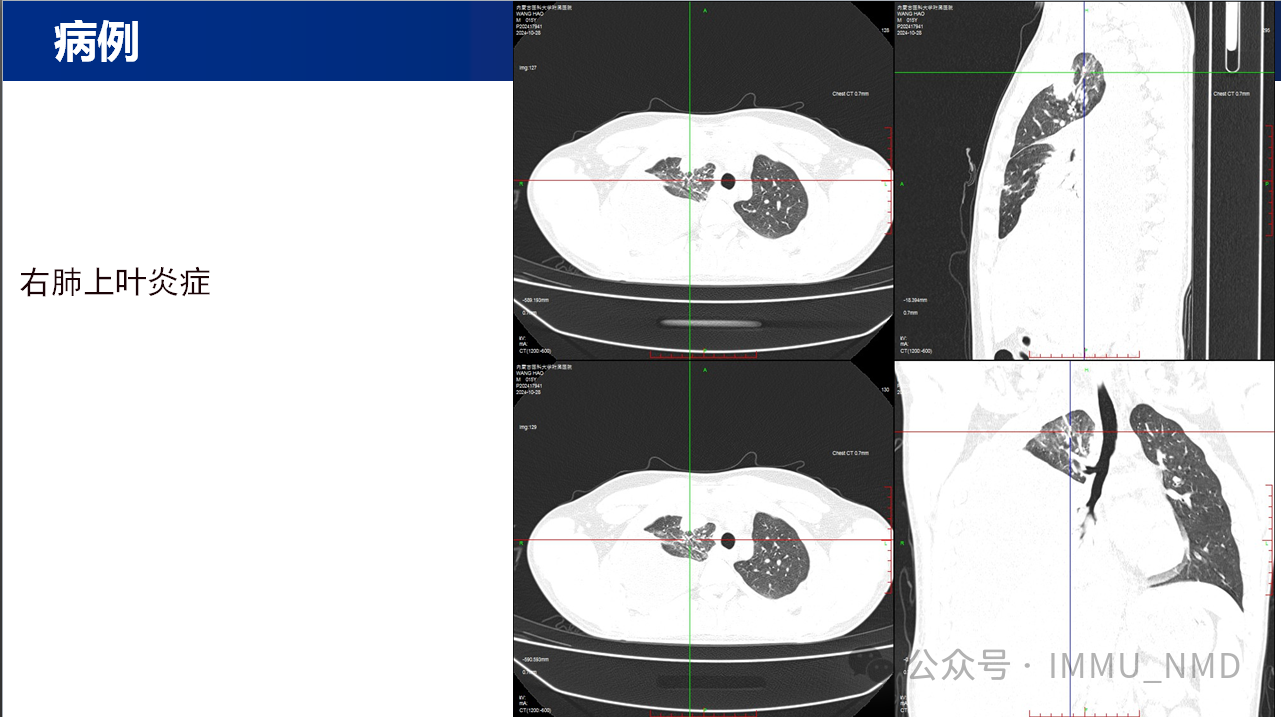

2025年2月27日上午,由核医学科党支部和内蒙古自治区医学会核医学分会青年委员会共同组织的“核先锋”青年医师疑难病例读片会第二十七期暨内蒙古自治区医学会核医学分会青委会青年医师疑难病例读片会第七期于线上腾讯会议及线下核医学科示教室成功举办。参加线下读片会的有党支部的全体党员医生及非党员医生、研究生、规培生、进修生,参加线上读片会的有青委会多名医生,读片会由张国建教授做最后总结。